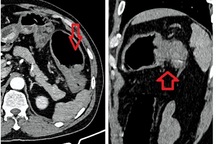

TS.BS Phạm Văn Bình, Giám đốc Trung tâm phẫu thuật nội soi Robot, Bệnh viện K trung ương (Hà Nội): Với ung thư đại trực tràng, đặc biệt là ung thư đại tràng, giai đoạn đầu các triệu chứng sớm rất nghèo nàn, chủ yếu vẫn tập trung vào các rối loạn tiêu hoá như: táo bón, ỉa chảy, đôi khi đi ngoài ra máu, khuôn phân nhỏ, nhiều khi chỉ là đầy chướng bụng, rối loạn thói quen đi ngoài.

Ở giai đoạn muộn hơn thì có dấu hiệu đau bụng, bán tắc ruột, bệnh nhân có thể sút cân, suy nhược, mệt mỏi, thể trạng chung kém.

Như đã nói ở trên, ở giai đoạn sớm dấu hiệu của bệnh là rối loạn về tiêu hóa. Đi ngoài ra máu là một trong những triệu chứng sớm. Khi có triệu chứng này thì đã là cảnh báo, thường chúng ta phải nắm bắt được để đi sàng lọc và khám. Đợi khi đã đau rồi thì giai đoạn không còn là giai đoạn sớm nữa. Bởi vì bản chất của đau là khối u đã to, chèn ép, có bán tắc ruột hoặc di căn đến nơi khác có chèn ép thì mới gây đau.

Với trường hợp ông bạn, ngay giai đoạn ban đầu có đi ngoài ra máu là triệu chứng cảnh báo sớm của bệnh, nếu như đi khám sớm thì có thể chẩn đoán ngay bệnh ở giai đoạn tốt hơn rất nhiều. Còn khi để muộn, thời gian dài thì ung thư có tiến triển, đặc biệt trong trường hợp này là ung thư đã di căn gan. Điều này thật đáng tiếc.